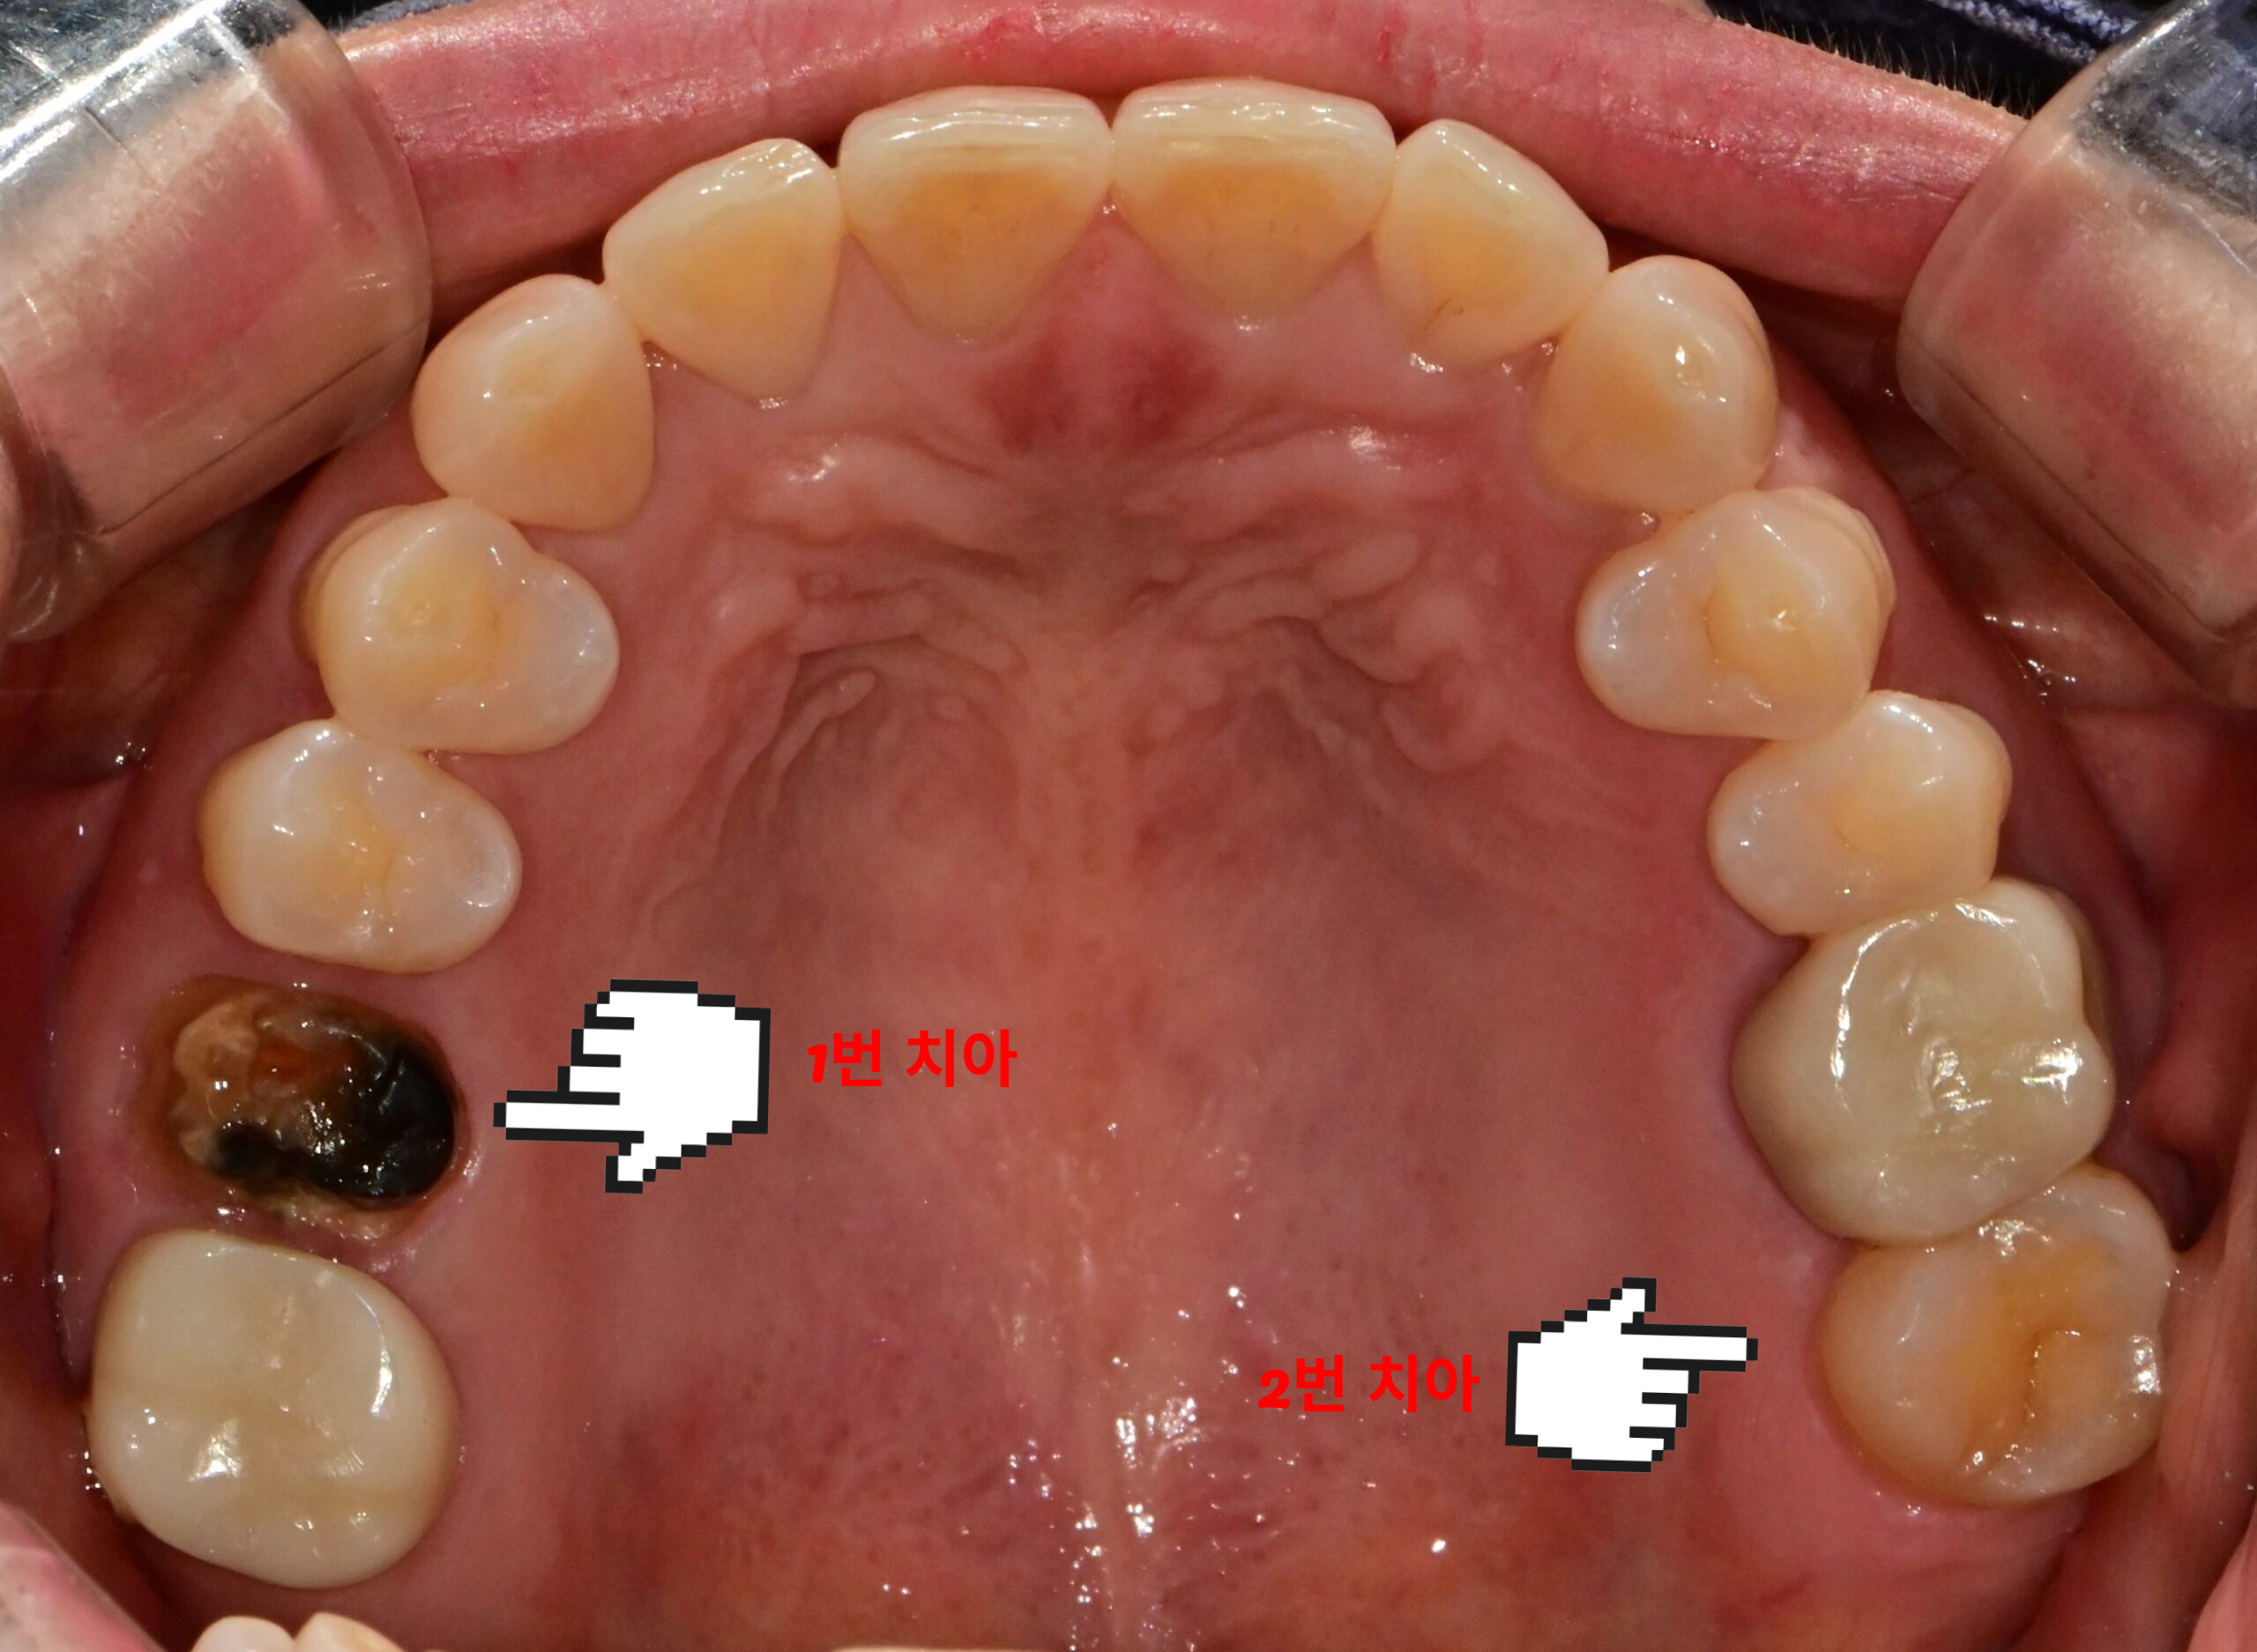

발치 판정 받은 치아, 신경치료와 크라운으로 살릴 수 있을까?

발치 판정 치아 치근단 X-ray 진단 신경관 막힘 화살표 표시

좋은 진료를 정직하게 | 선한 영향력으로 더 나은 가치를 발치 판정 받은 치아, 신경치료와 크라운으로 살릴 수 있을까? 강서구 마곡 서울쏙쏙치과 꿈꾸는 쏙쏙 치과의사 박상억입니다^^ 안녕하세요^^ 오늘은 발치 판정 치아를 어떻게 치료할 수 있을지 이야기해 보려 합니다! 어느 날 간단한 문제라 생각하고 치과에 갔는데 진단을 받아보니 발치를 해야 한다는 말을 들었다면 그 충격은 상당할 겁니다. … 더 읽기